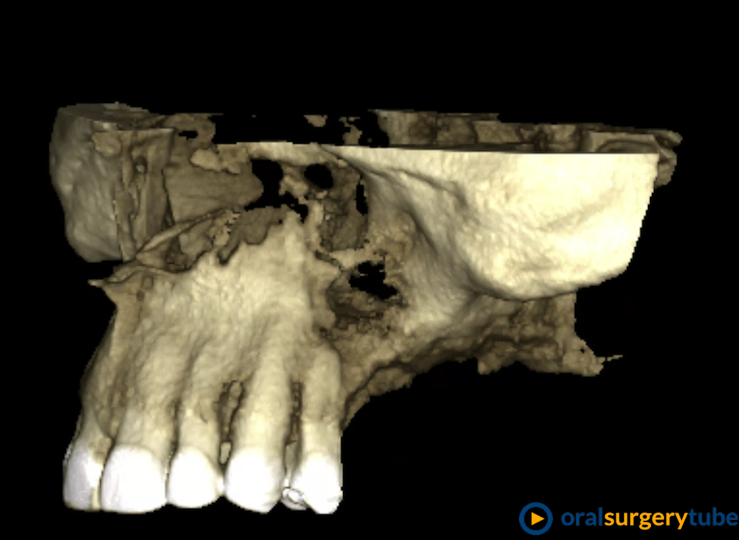

Comunicación Bucosinusal tras elevación de seno